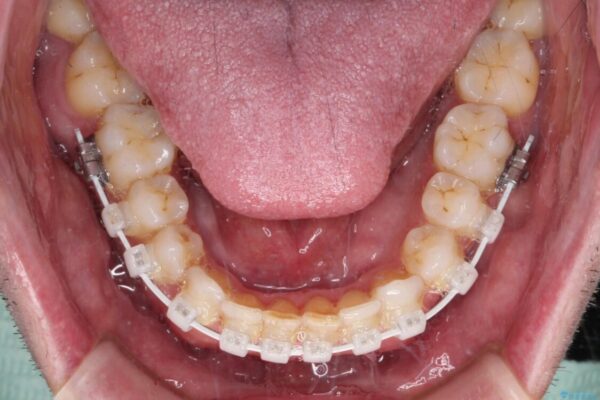

治療途中

• 前歯でものを噛みきりたい 目立たない装置でのワイヤー矯正 治療途中画像